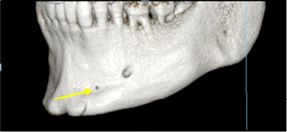

Oval and round shapes were taken as evaluation criteria, as well as the presence of accessory holes (Figure 4).

Figure 4: Presence of accessory mental foramina

Accessory holes were found in 100 cases (55.5%) out of the 180 tomographies taken (Table V).

Accessory mental foramina were present in 55.5% of all cases, which differs from the results of most studies conducted on dry mandibles and evaluated using cone-beam CT (6, 14, 15, 20, 23). Singh R. & Srivastav observed the presence of accessory holes in 13% of the total population evaluated, while other studies (6, 14, 15, 23) showed a prevalence of 6.67%, 6.6%, 3.92% and 6.5% respectively.

Oval and round shapes were taken as evaluation criteria, as well as the presence of accessory holes (Figure 4).

Figure 4: Presence of accessory mental foramina

Accessory holes were found in 100 cases (55.5%) out of the 180 tomographies taken (Table V).

Accessory mental foramina were present in 55.5% of all cases, which differs from the results of most studies conducted on dry mandibles and evaluated using cone-beam CT (6, 14, 15, 20, 23). Singh R. & Srivastav observed the presence of accessory holes in 13% of the total population evaluated, while other studies (6, 14, 15, 23) showed a prevalence of 6.67%, 6.6%, 3.92% and 6.5% respectively.